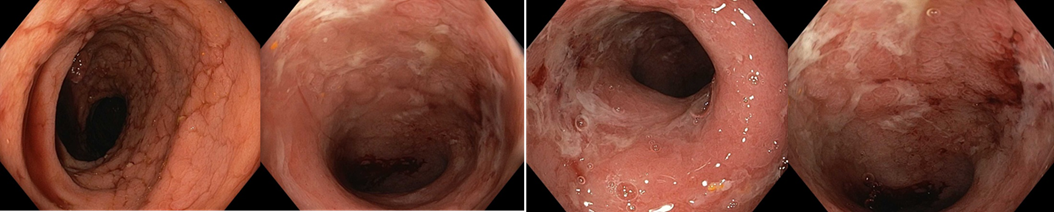

Koloskopie 2012/2: Endoskopický obraz Crohnovské pankolitidy, středně těžké až těžké (více je postižen P tračník), normální terminální ileum

2012/10 Endoskopický obraz mírné segmentální kolitidy charakteru Crohnovy choroby (rozsah postižení je 10-20 % tračníku) - podstatné zlepšení proti předchozímu nálezu, ke slizničnímu zhojení nedošlo

Koloskopie: Endoskopický obraz těžké segmentální kolitidy

2013/11 endoskopický obraz těžké pankolitidy charakteru Crohnovy choroby   - obraz cobble stones relativně je ušetřeno rektum, kde je ložiskově patrná   podslizniční cévní kresba

Koloskopie: Endoskopický kolitidy s ušetřením rekta, maximálním postižením v P tračníku – dle obrazové dokumentace zlepšení ve všech etážích tračníku   (i v P tračníku rozsah ulcerací snížen cca o 50%)

Koloskopie: edém, eroze, ulcerace, zánětlivé polypy v terénu po zánětlivých změn